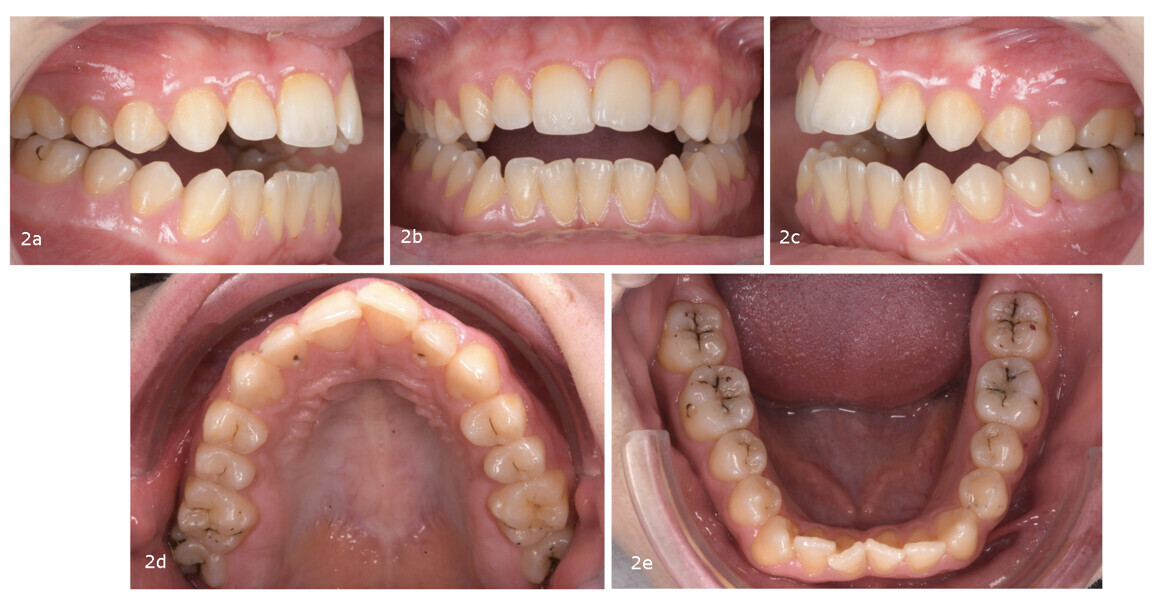

The occlusal analysis revealed a Class II Division 2 malocclusion, along with an anterior open bite tendency, insufficient overjet and overbite, maxillary and mandibular constriction, negative torque in both the posterior segments and maxillary incisors, a pronounced curve of Spee and severe crowding in both arches. The dental midlines were not centred. The mandibular midline deviated to the left, primarily owing to the inclination of the mandibular incisors. Despite having a favourable gingival biotype and adequate attached gingiva, the patient presented with localised gingival recession and abfraction lesions—most likely the result of occlusal instability and functional overload (Fig. 18).